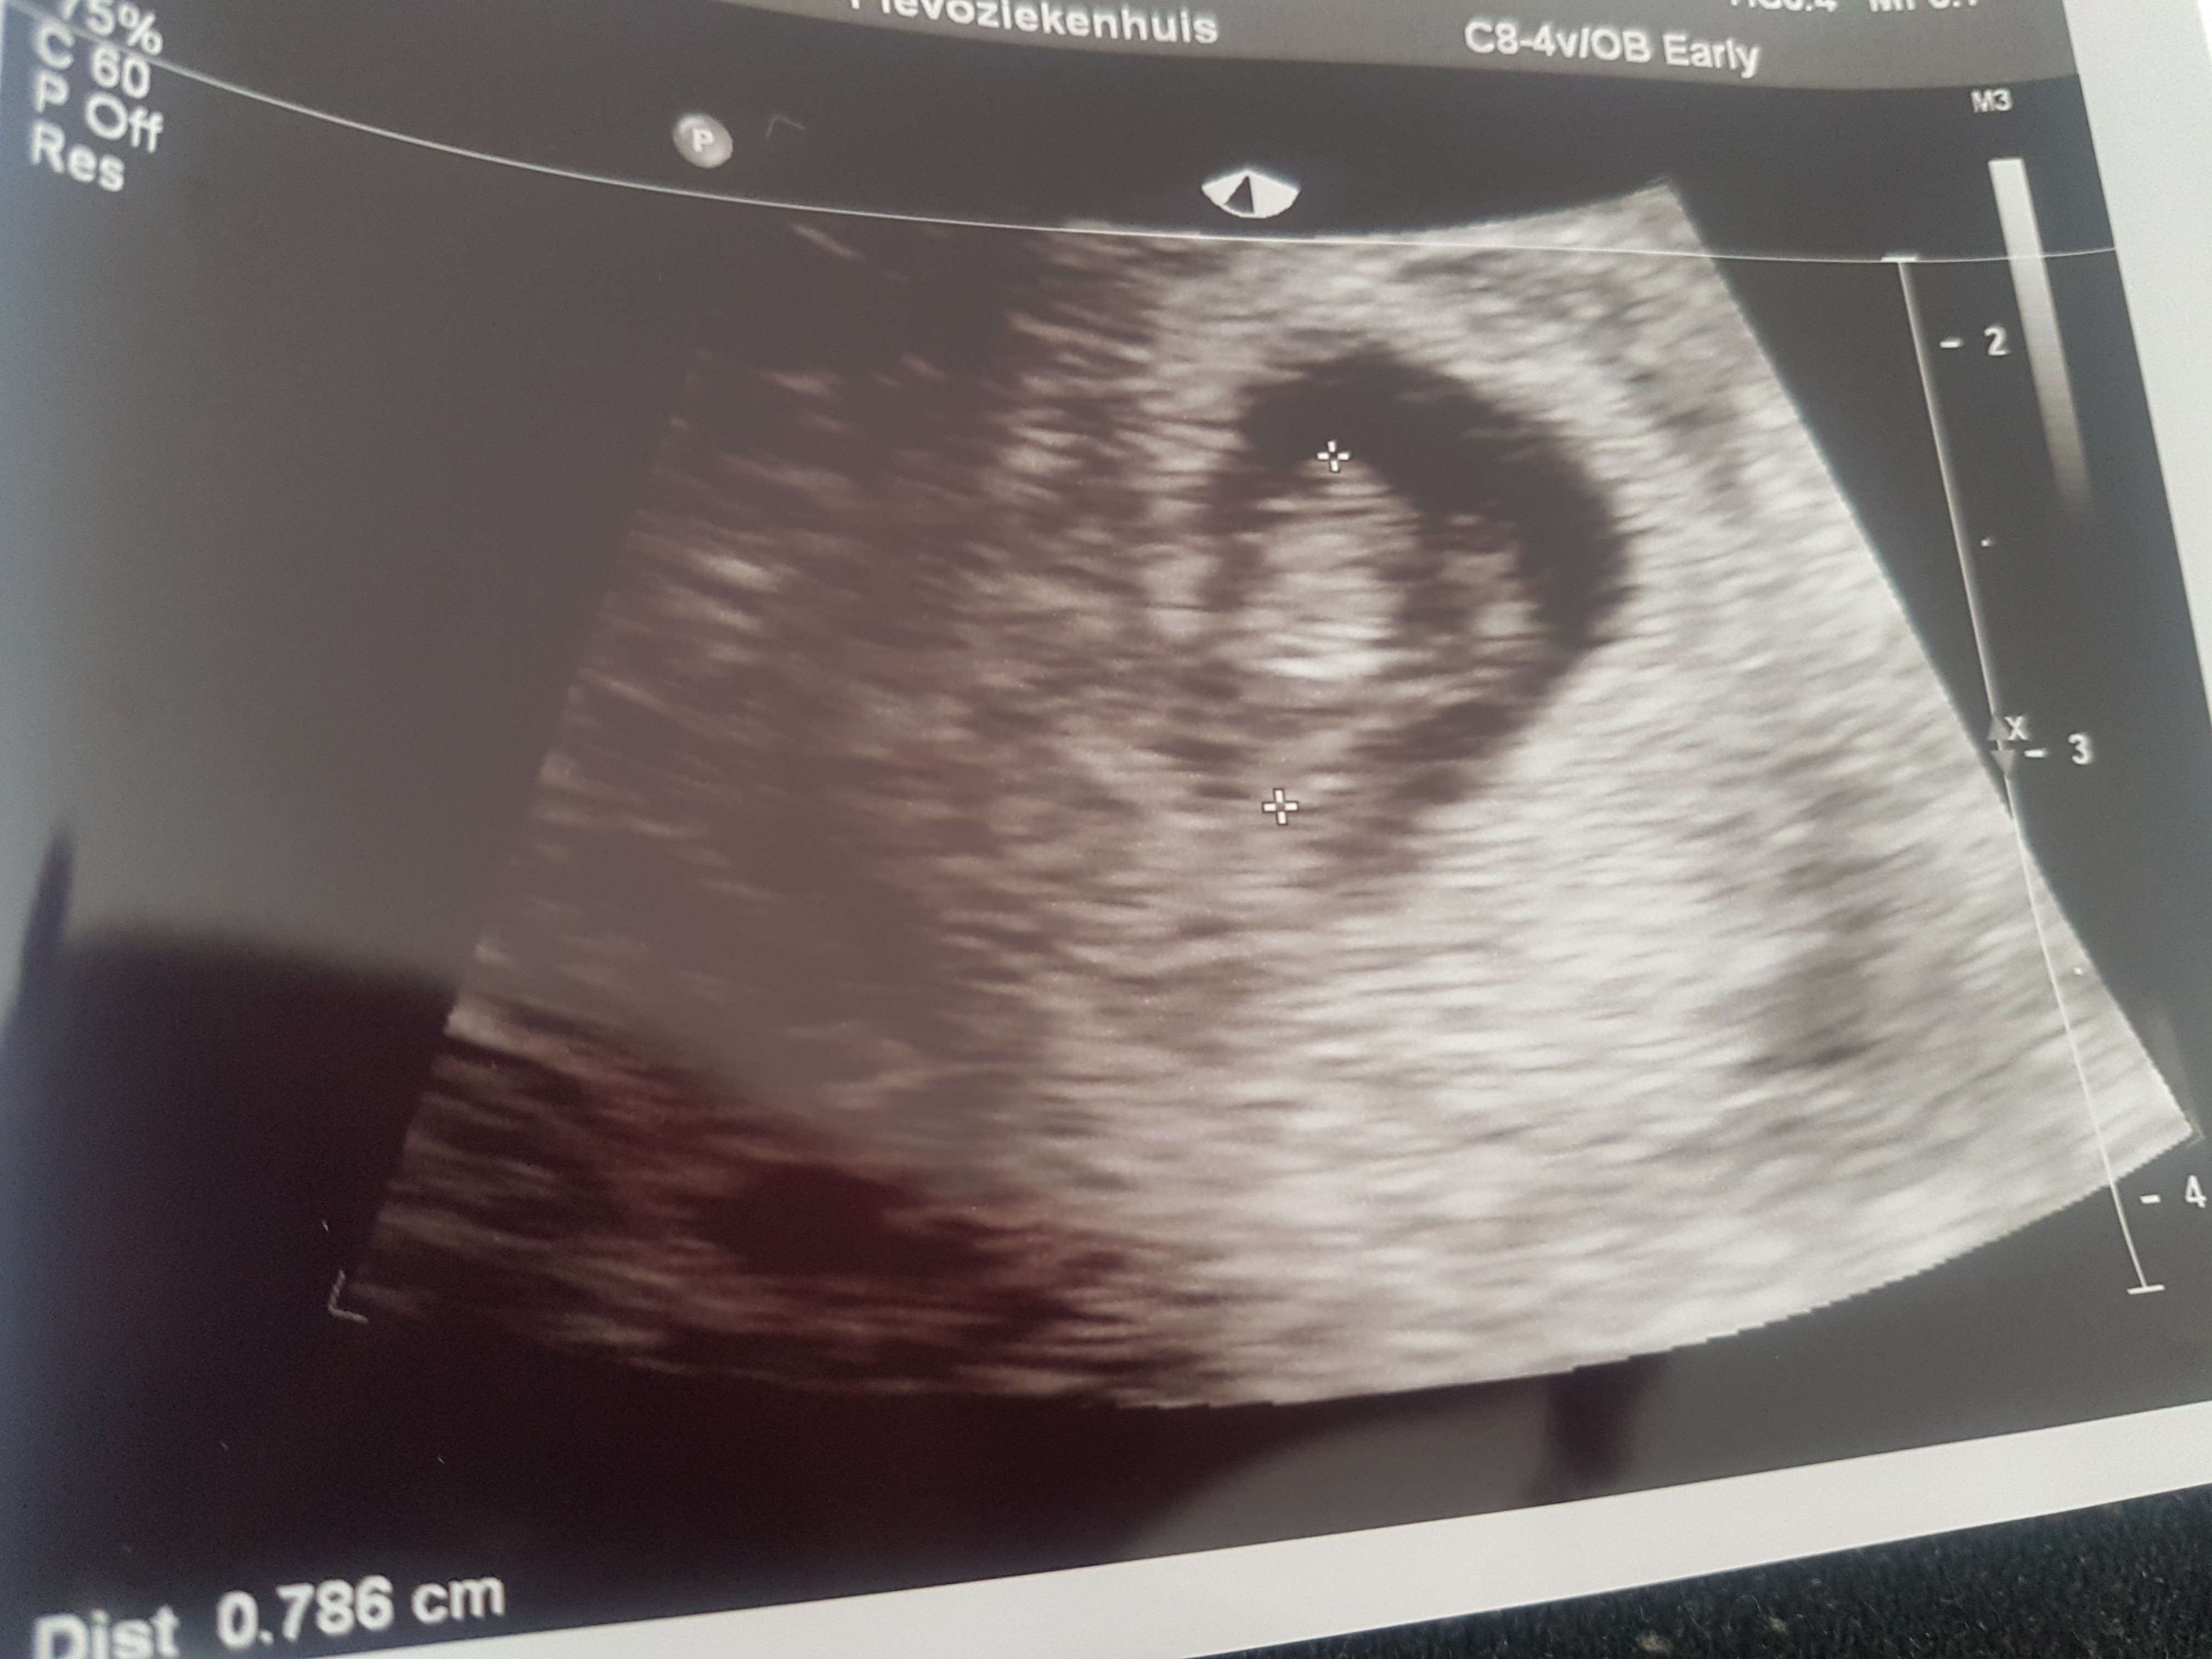

Zobacz załącznik 1012067